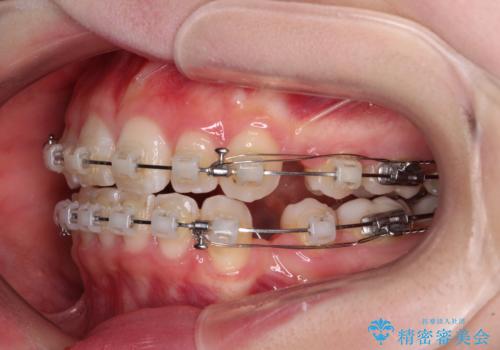

- 矯正装置

- クリアブラケット

- 2年4ヶ月

- 10-30回